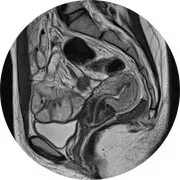

Pendant l’IRM, vous êtes allongé sur la table d’examen, généralement sur le dos. Une antenne est placée au niveau de l’organe à visualiser, puis vous êtes introduit dans l’appareil (semblable à un tunnel). Au cours de l’examen, un produit de contraste est parfois injecté dans une veine du bras pour améliorer la qualité des images : ce geste n’est pas plus douloureux qu’une prise de sang. Il faut rester allongé, à l’intérieur de l’appareil, durant toute la durée de l’examen, ce qui peut engendrer un sentiment de malaise (claustrophobie).

L’examen est également bruyant : le bruit est similaire à celui du moteur d’un bateau ou d’un tam-tam. Pour réduire ce bruit, l’équipe médicale vous fournit un casque pendant l'examen. Une IRM dure, en général, de 20 à 30 minutes au cours desquelles il est demandé de rester immobile. Si nécessaire (malaise du patient, claustrophobie trop importante), les radiologues peuvent intervenir ou interrompre l’examen à tout moment. Il vous sera remis une sonnette et vous pourrez à tout moment communiquer avec les manipulateurs en radiologie présents dans la salle.